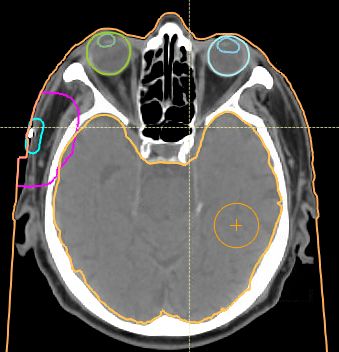

| allgemeines | Zum Bearbeiten der ROIs gibt es eine Reihe von Werkzeugen (Tools)![]() | ||||